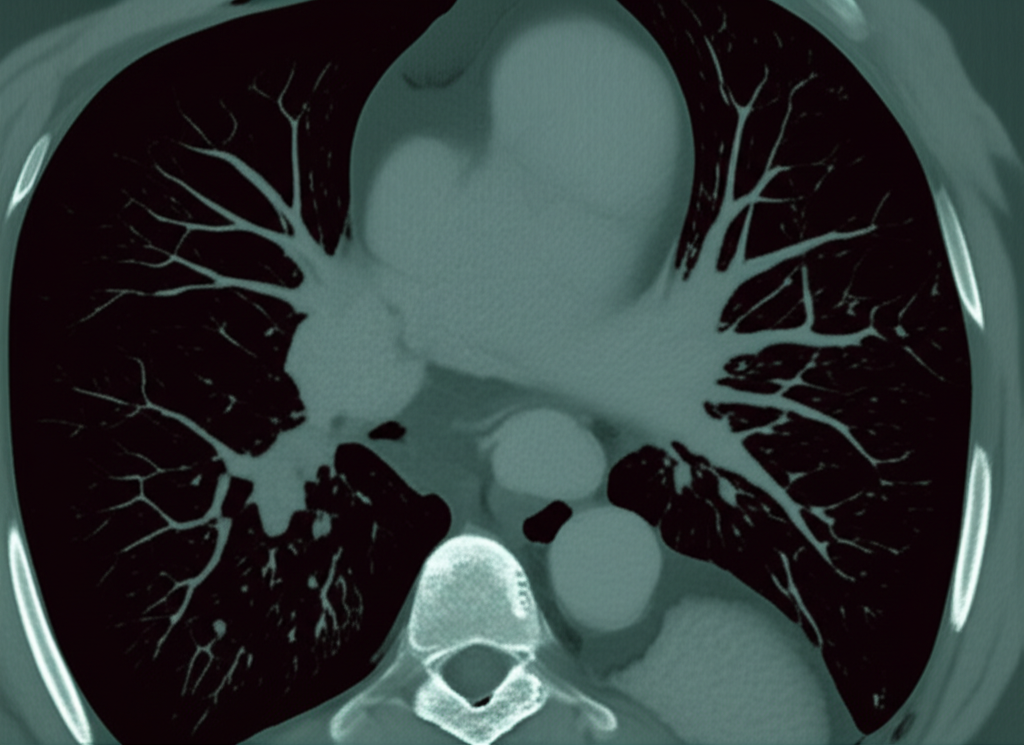

심장 CT(Computed Tomography)는 컴퓨터 단층 촬영 기술을 이용하여 심장의 단면 영상을 얻는 검사입니다. 기존의 엑스레이 촬영보다 훨씬 더 자세하고 정확한 이미지를 제공하여, 심장 질환의 조기 진단과 치료 계획 수립에 큰 도움을 줍니다. 심장 CT는 특히 관상동맥 질환, 심장 판막 질환, 심근 질환 등 다양한 심장 질환을 진단하는 데 유용합니다.

- 관상동맥 질환 진단: 관상동맥 CT는 관상동맥의 협착이나 폐쇄 여부를 정확하게 진단할 수 있습니다. 특히, 칼슘 스코어링을 통해 동맥경화의 정도를 평가하고, 향후 심혈관 질환 발생 위험을 예측할 수 있습니다.

- 심장 구조 평가: 심장의 크기, 모양, 위치 등을 정확하게 파악하여 심장 비대, 심방중격결손, 심실중격결손 등 선천성 심장 질환이나 심장 구조 이상을 진단할 수 있습니다.